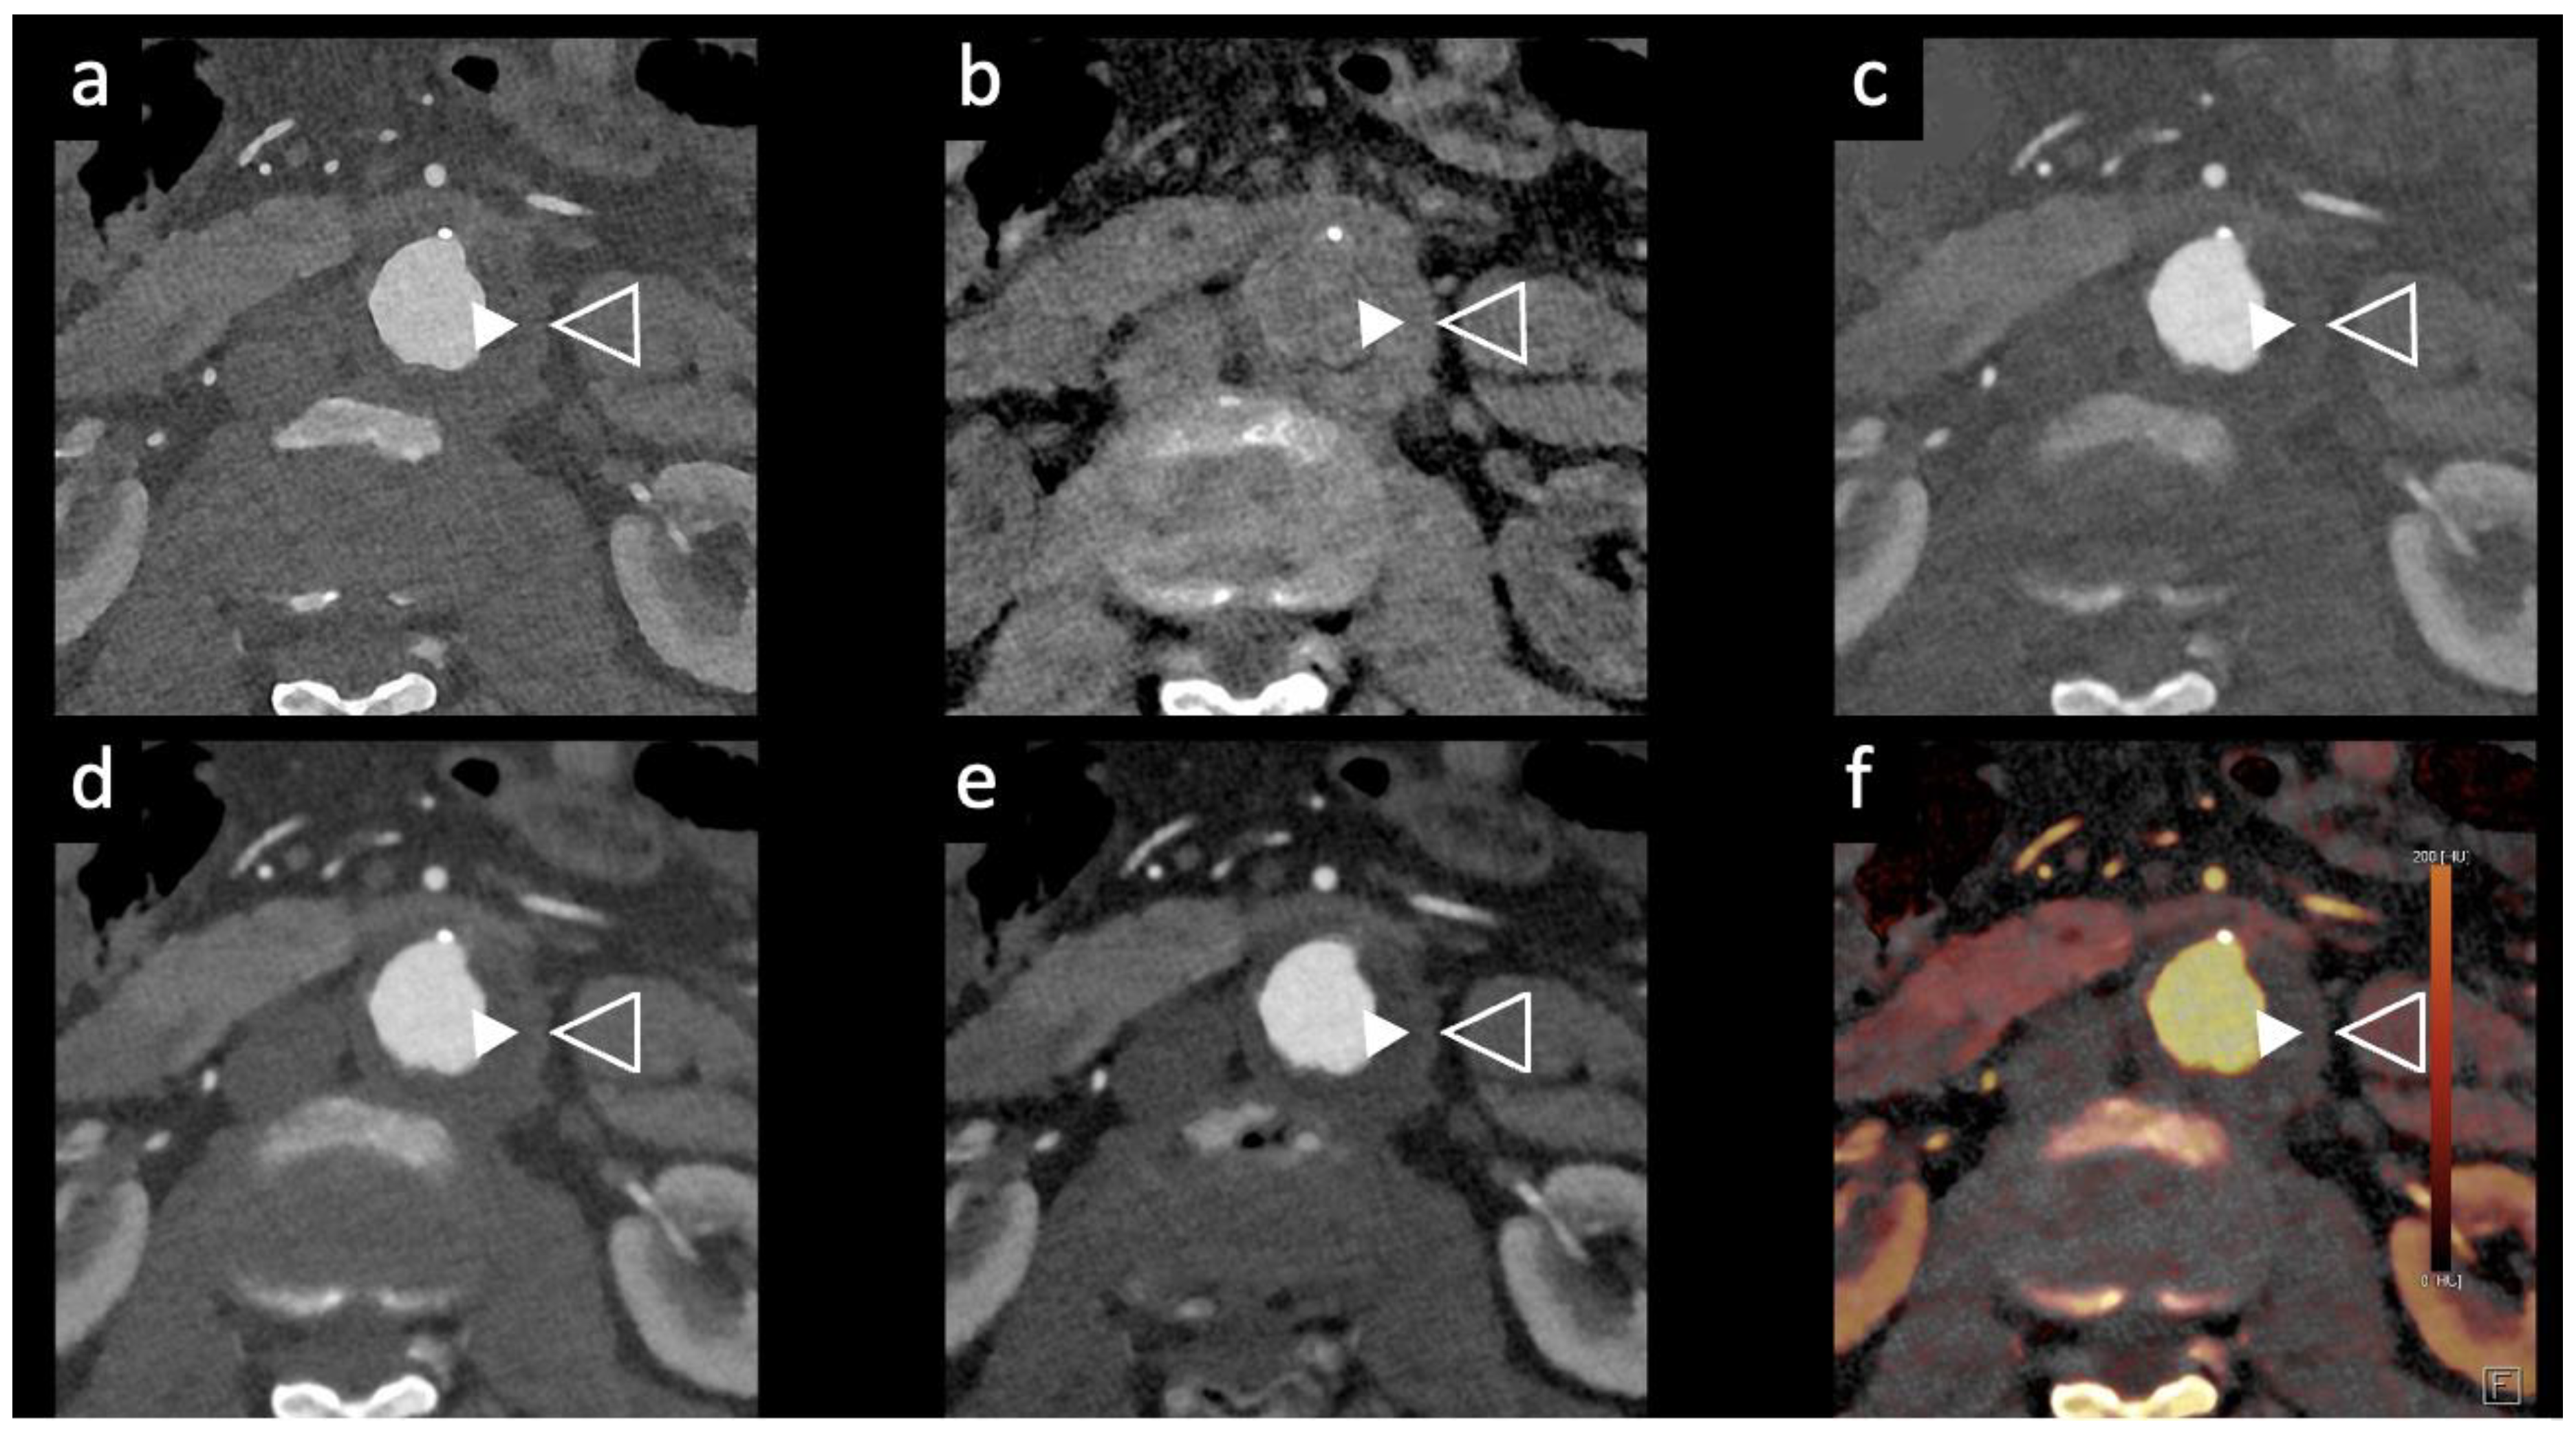

- PCCT can improve endoleak detection and characterization after EVAR with reduced radiation exposure using bicolor K-edge imaging and dual contrast agents.

- Turrion Gomollon, A. M.; Mergen, V.; Sartoretti, T.; Polacin, M.; Nakhostin, D.; Puippe, G.; Alkadhi, H.; Euler, A. Photon-Counting Detector CT Angiography for Endoleak Detection After Endovascular Aortic Repair. Invest Radiol 2023. [CrossRef]

- Cosset, B.; Sigovan, M.; Boccalini, S.; Farhat, F.; Douek, P.; Boussel, L.; Si-Mohamed, S. A. Bicolor K-Edge Spectral Photon-Counting CT Imaging for the Diagnosis of Thoracic Endoleaks: A Dynamic Phantom Study. Diagn Interv Imaging 2023, 104 (5), 235–242. [CrossRef]